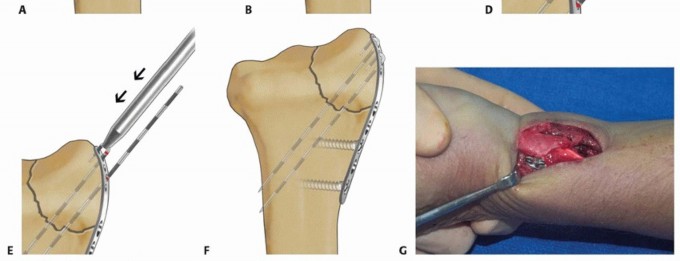

Limited-Incision Volar Approach

Make a longitudinal incision along the radial side of the radial artery.

Proximally, insert the tip of a tenotomy scissors over the surface of the first dorsal compartment sheath and sweep distally to elevate a radial skin flap.

Pronate the forearm and sharply expose the bare area of bone over the radial styloid situated in the interval between the first and second dorsal compartments ( TECH FIG 1A).

Leaving the distal 1 cm of sheath intact, open the first dorsal compartment proximally and mobilize the tendons. Reflect the insertion of brachioradialis to complete exposure of the radial column ( TECH FIG 1B).

TECH FIG 1 • Limited-incision volar approach. A. Sweeping tenotomy scissors to elevate radial skin flap off first dorsal compartment. B. Deep exposure of the radial column.